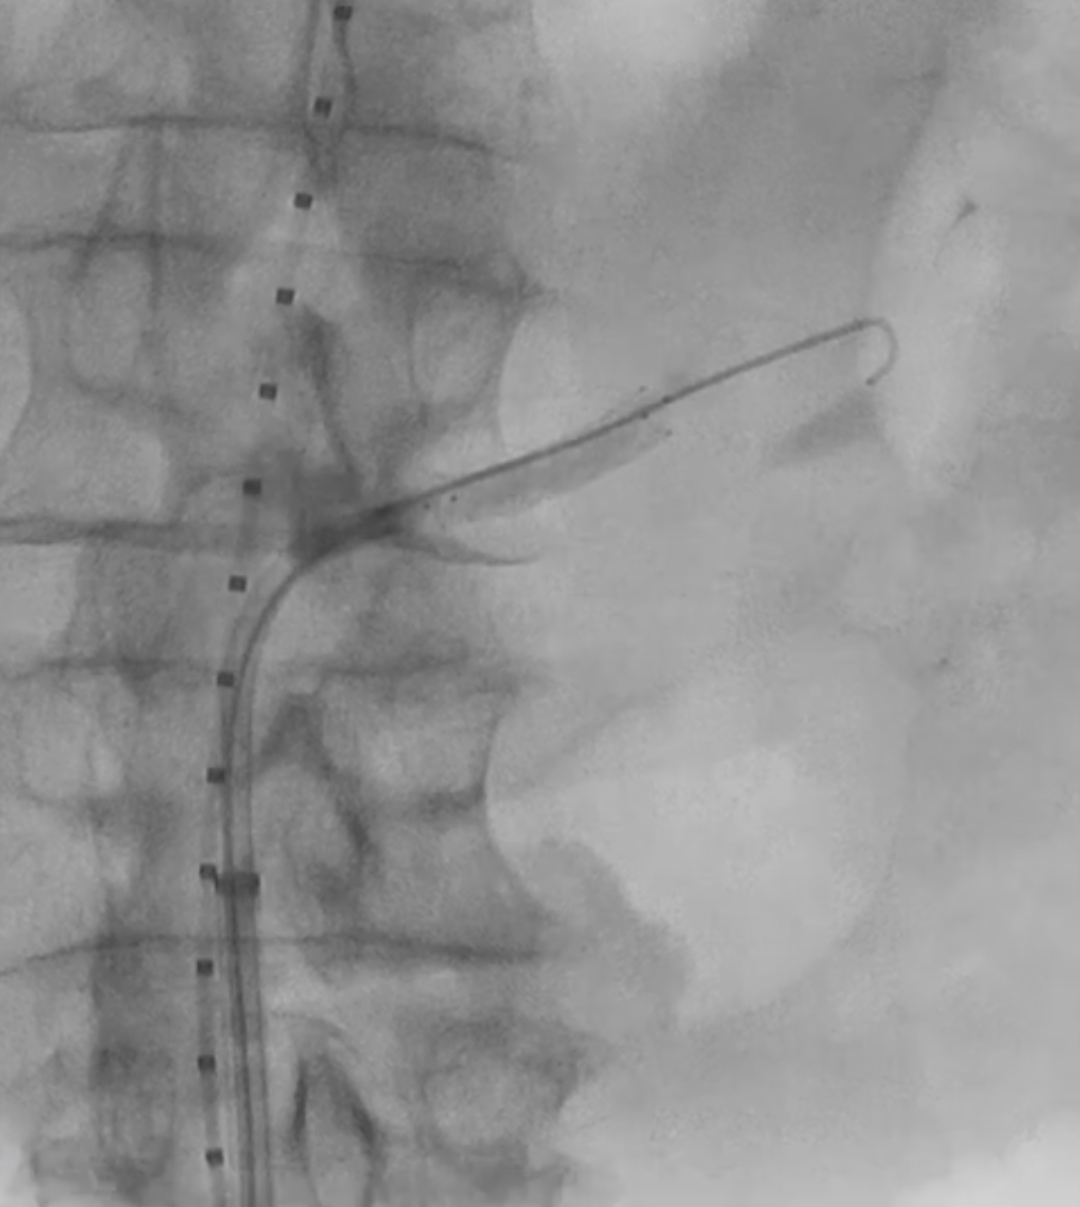

在植入主动脉支架后,首先开通SMA,配合可调弯导管调整激光导管角度,多角度视图下确保对准。发射激光(60-60mJ/mm2),激光穿透主体支架覆膜后立即推进导丝。

确认导丝进入靶血管后移除激光导管,依次使用4mm快交球囊、5mm切割球囊进行扩张开窗,交换入35系统导丝,在预植入的支架内引入VBX球扩覆膜支架,远端超过预植入支架远端,近端伸入主动脉3-5毫米,扩张球囊使VBX释放。

再次扩张VBX支架近端使其锚定于主动脉支架上。

造影确认开窗支架的通畅性。